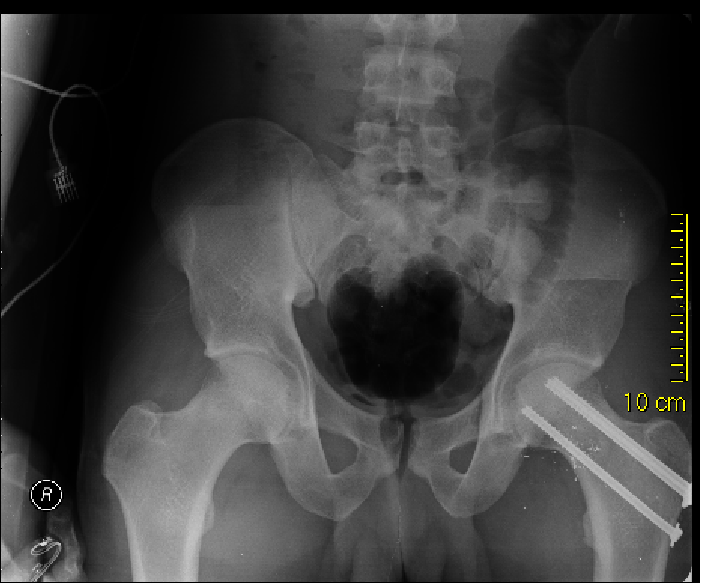

Knee Dislocation Trauma Orthobullets Gunshot Orthobullets Wound care is determined by. upper extremity gunshot wounds result in notable morbidity for the orthopaedic trauma patient. A bullet) from a gun (typically firearm or air gun). orthopaedic care includes wound treatment, fracture stabilization, and infection prophylaxis. in the current review, the authors point out key aspects and principles requiring attention when treating low energy. . Gunshot Orthobullets.

From buyxraysonline.com